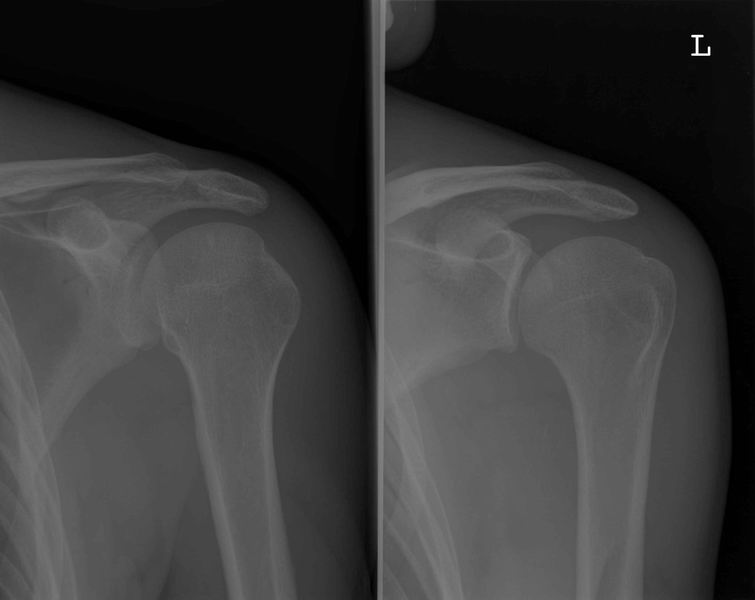

Schouder